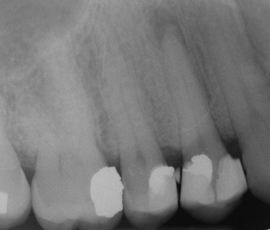

The report shows that oral conditions affect as many as 3.9bn people worldwide – over half the total population. Untreated tooth decay or cavities in permanent teeth - also known as dental caries - was the most common of all 291 major diseases and injuries assessed by the GBD 2010 study, affecting 35 per cent of the world population.

The study found that the global burden of oral conditions is shifting from severe tooth loss towards severe periodontitis and untreated caries. It found that the global burden of oral diseases increased 20 per cent between 1990 and 2010, while a reduction of 0.5 per cent was observed for all conditions together. This increase was mainly due to population growth and ageing.